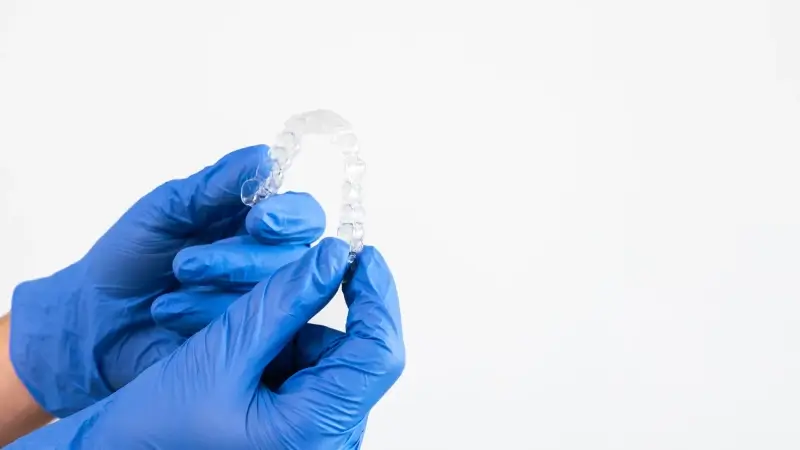

Leczenie nakładkowe, znane również jako terapia ortodontyczna z wykorzystaniem przezroczystych nakładek, zyskuje coraz większą popularność wśród pacjentów pragnących poprawić swój uśmiech. Skutki tego rodzaju leczenia mogą być różnorodne i zależą od wielu czynników, takich jak stopień skomplikowania wad zgryzu oraz zaangażowanie pacjenta w proces leczenia. W pierwszej kolejności warto zauważyć, że nakładki są mniej inwazyjne niż tradycyjne aparaty ortodontyczne, co sprawia, że wiele osób decyduje się na tę metodę. Dzięki ich przezroczystości, pacjenci mogą czuć się bardziej komfortowo w sytuacjach społecznych. Jednakże skutki leczenia nakładkowego nie ograniczają się tylko do estetyki. Wiele osób zgłasza poprawę funkcji żucia oraz zmniejszenie bólu związane z wadami zgryzu. Zmiany te mogą prowadzić do lepszego samopoczucia oraz większej pewności siebie.

Leczenie nakładkowe ma swoje niezaprzeczalne zalety oraz pewne wady, które warto rozważyć przed podjęciem decyzji o terapii ortodontycznej. Do głównych zalet należy niewątpliwie estetyka – przezroczyste nakładki są praktycznie niewidoczne dla innych ludzi, co sprawia, że pacjenci czują się bardziej komfortowo podczas noszenia ich w codziennym życiu. Dodatkowo nakładki można łatwo zdjąć podczas jedzenia czy mycia zębów, co ułatwia utrzymanie higieny jamy ustnej w porównaniu do tradycyjnych aparatów metalowych. Kolejną zaletą jest możliwość szybszego dostosowania planu leczenia dzięki nowoczesnym technologiom cyfrowym stosowanym przy projektowaniu nakładek. Niemniej jednak istnieją także pewne wady związane z tą metodą leczenia. Na przykład nie wszystkie przypadki ortodontyczne nadają się do terapii za pomocą nakładek; bardziej skomplikowane wady mogą wymagać tradycyjnych aparatów ortodontycznych dla uzyskania optymalnych rezultatów. Ponadto sukces leczenia zależy od zaangażowania pacjenta – konieczne jest noszenie nakładek przez co najmniej 22 godziny dziennie, co może być wyzwaniem dla niektórych osób.